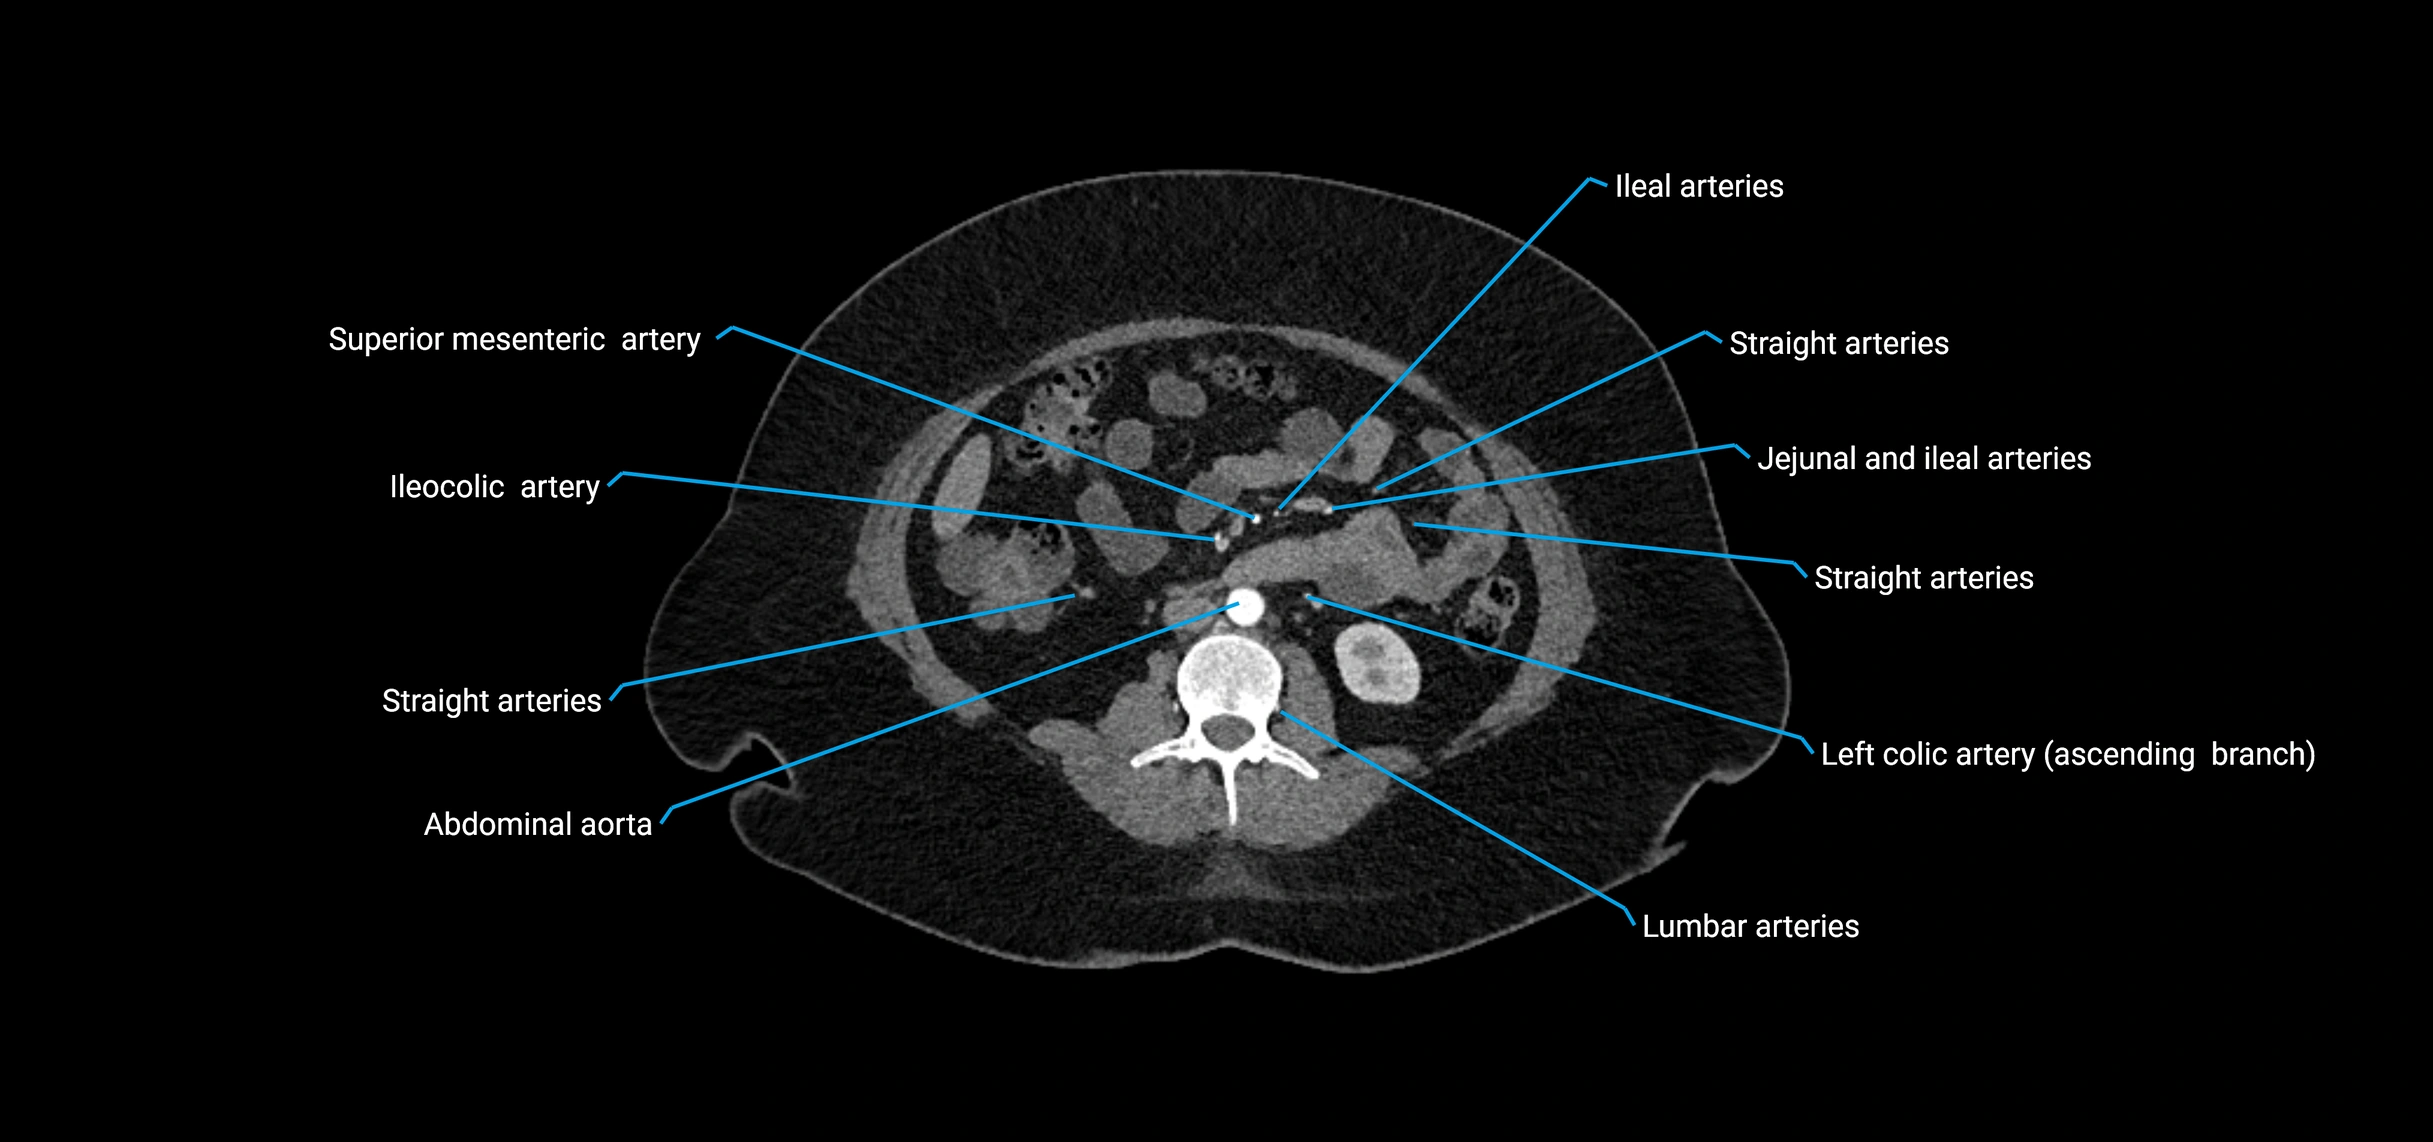

CT Appearance

Non-contrast CT:

• Appears as a tubular soft tissue structure anterior to vertebral bodies

• Calcified atherosclerotic plaques appear as hyperdense foci along the wall

• Useful for screening abdominal aortic aneurysm (AAA) size and mural calcification

Contrast-enhanced CT (CTA):

• Gold standard for abdominal aortic imaging

• Provides excellent detail of lumen, wall, aneurysm, thrombus, and branch vessels

• Multiplanar and 3D reconstructions help in aneurysm measurement, stent graft planning, and dissection evaluation

• Detects acute rupture, traumatic injury, or occlusion with high sensitivity